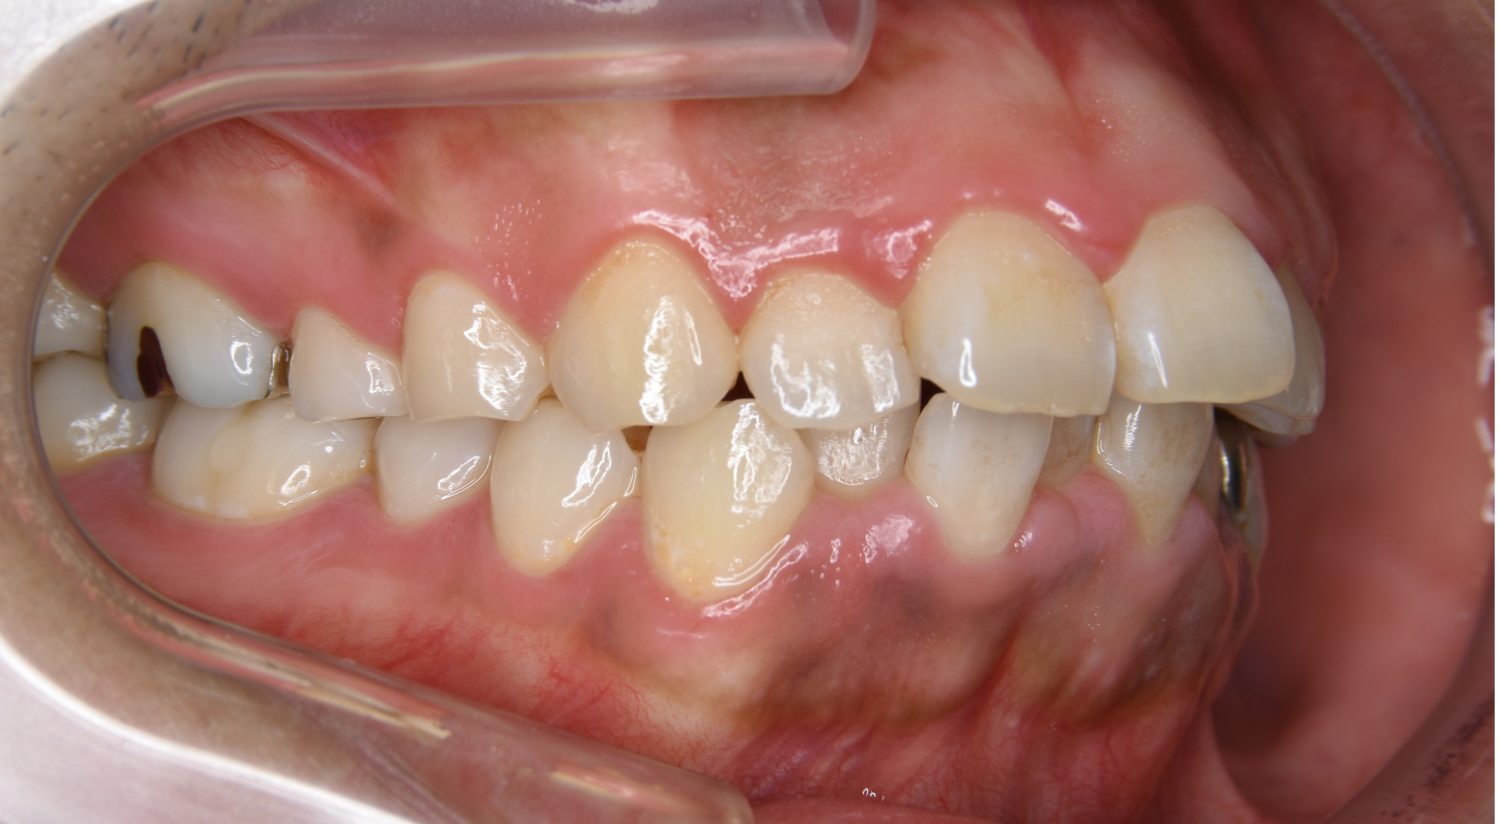

上顎前突の症例紹介②

Before

主訴

出っ歯を治したい。

治療内容

上顎両側第一小臼歯を抜歯し、上下ラビアルブラケット(唇側装置)にて治療を行いました。

治療費

1,000,000 円(税込)

治療期間

25ヶ月

通院回数

25回

想定されたリスク

※なし

上顎前歯の前突により口元の突出が認められました。上の左右の第一小臼歯を抜歯し上顎前歯を後退させることで口元の突出感は改善し、咬合も良好な状態となりました。